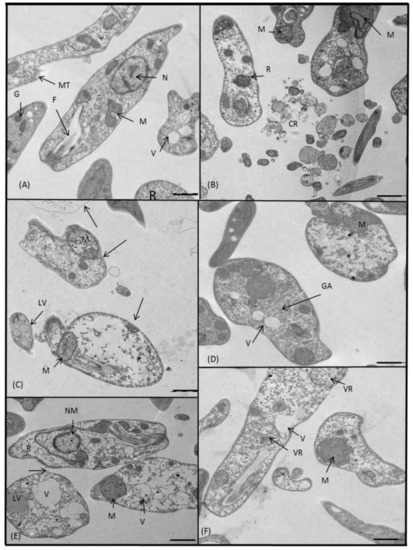

2.3.3. Microscopy

4.5. Ultrastructural Alterations